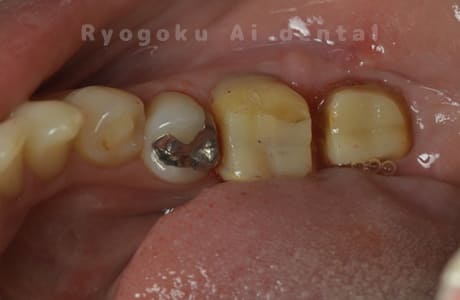

Case09

-

部分矯正クラウンレングスニング正面術前

部分矯正クラウンレングスニング正面術中

部分矯正クラウンレングスニング正面術後

部分矯正 クラウンレングスニング 咬合面術前

部分矯正 クラウンレングスニング 咬合面術中

部分矯正 クラウンレングスニング 咬合面術後/p>

歯根端切除術中

歯根端切除術直後

歯根端切除術後

マイクロエンド術前

マイクロエンド術後

- 原因

- パーフォレーション、慢性根尖性歯周炎

- 治療内容

- マイクロエンド、MTM、クラウンレングスニング、歯根端切除術

- 治療費用

- 286,000円

他院で歯の根の中に穴が空いているとのことで抜歯と診断された患者様です。一部穴が空いている部分を修復し、部分矯正を行い、手術を行いました。経過良好で、患者様も満足されています

<リスク・副作用>

手術後は痛み、腫れ、痺れ、青あざなどの副作用が生じます。痛みは痛み止めを処方しますが、腫れ、青あざは1週間程度生じる場合があります。また、部位によっては神経の走行が複雑で、痺れが残り、長期的にお薬を処方する場合があります。